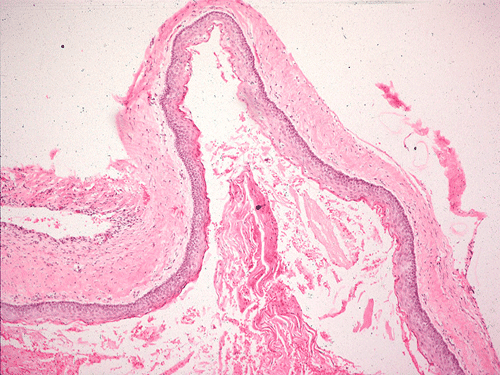

The sinus on the left side is opacified and contains a tooth. There does not seem to be significant destruction of the surrounding bone on this plain film.

A tooth is present in the specimen. The soft tissue component consists of keratinizing squamous epithelium of rather even thickness of about 5-8 cells thick supported by a fibrous stroma without significant inflammatory cell infiltration (Panel B & C). Keratinaceous debris shredding from the surface of the epithelium is noted. Note that parakeratosis (retention of nuclei in the keratinized layer) is present  (Panel C). Good polarization is noted in the epithelium although there are some basal hyperplasia and palisading arrangement of the basal layers. The nuclear looks slightly immature and some with a small but distinct nucleoli. These are features of some low grade dysplasia.